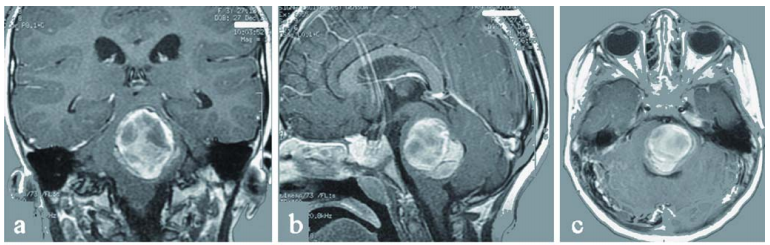

脑膜瘤作为最常见的轴外原发性脑肿瘤,约占所有颅内原发肿瘤的13%-19%。其生物学行为高度依赖于肿瘤大小、解剖位置、与神经血管结构的毗邻关系及组织病理学特征。...